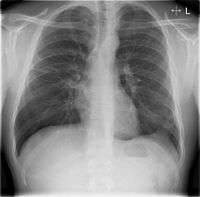

When signs are discovered, chest X-rays, examination of the blood and sputum for infectious microorganisms and blood tests are commonly used to diagnose CAP. Diagnostic tools depend on the severity of illness, local practices and concern about complications of the infection. All patients with CAP should have their blood oxygen monitored with pulse oximetry. In some cases, arterial blood gas analysis may be required to determine the amount of oxygen in the blood. A complete blood count (CBC) may reveal extra white blood cells, indicating infection.

Chest X-rays and X-ray computed tomography (CT) can reveal areas of opacity (seen as white), indicating consolidation. CAP does not always appear on x-rays, because the disease is in its initial stages or involves a part of the lung an x-ray does not see well. In some cases, chest CT can reveal pneumonia not seen on x-rays. X-rays can often mislead, as Heart failure or other types of lung damage can mimic CAP on x-rays.[12]

X-ray findings indicating hospitalization include:

- Involvement of more than one lobe of the lung

- Presence of a cavity

- Pleural effusion